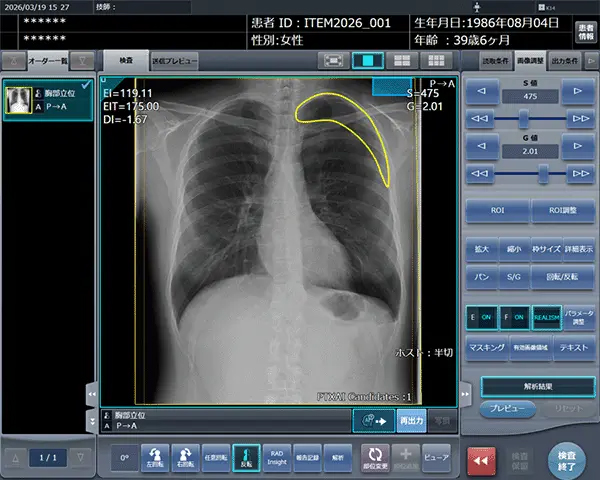

「STAT Link」は、気胸検出機能、所見報告・記録機能、「RADInsight(ラドインサイト)」との連携機能により、STAT画像所見報告のワークフローを包括的に支援する。

気胸の診断支援を行うプログラム「CXR Finding-i 気胸検出タイプ」と連携することで、ガイドラインにおいて一般撮影で診療放射線技師が発見した場合に報告すべきSTAT画像所見の一つに挙げられている気胸の候補を高精度で検出することができる。

ユーザー設定可能なテンプレートを活用した簡便な所見報告の記録機能を備え、診療放射線技師による迅速かつ正確な所見報告を支援し、報告業務の効率化と信頼性向上に貢献する。

一般撮影業務の最適化をサポートするシステム「RADInsight」との連携によりSTAT画像および報告データを蓄積し、診療放射線技師のスキル向上に役立てることで、医療現場での教育にも活用が期待できる。

「CXR Finding-i 気胸検出タイプ」は、胸部単純X線画像をAI※2で解析することで重要所見である気胸の候補を迅速に検出し、候補領域を画像上に表示することで見落とし防止を支援する。病変検出性能を示す指標である感度※3は95%と高い水準を実現していることに加え、気胸が存在しない画像をAIが正しく陰性(気胸なし)と判断した割合を示す特異度※4は96%であり、病変を見逃さないようにしつつ偽陽性も抑制した高精度の検出性能が特長である。